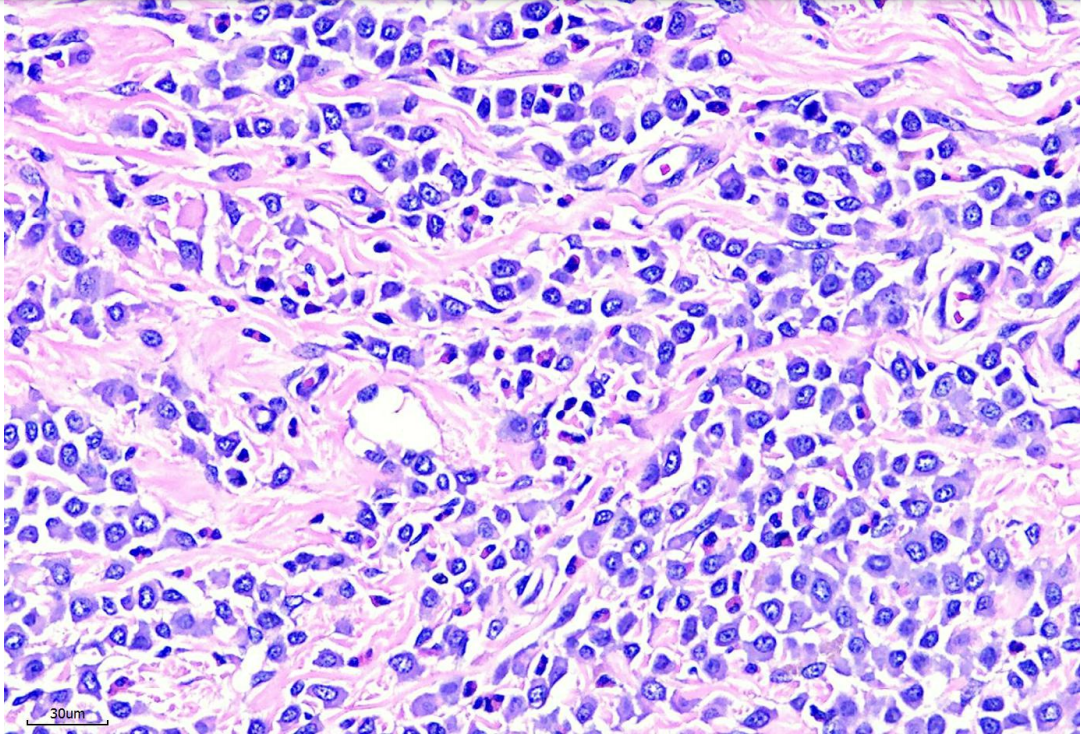

病理切片下確診為高惡性肥大細胞瘤